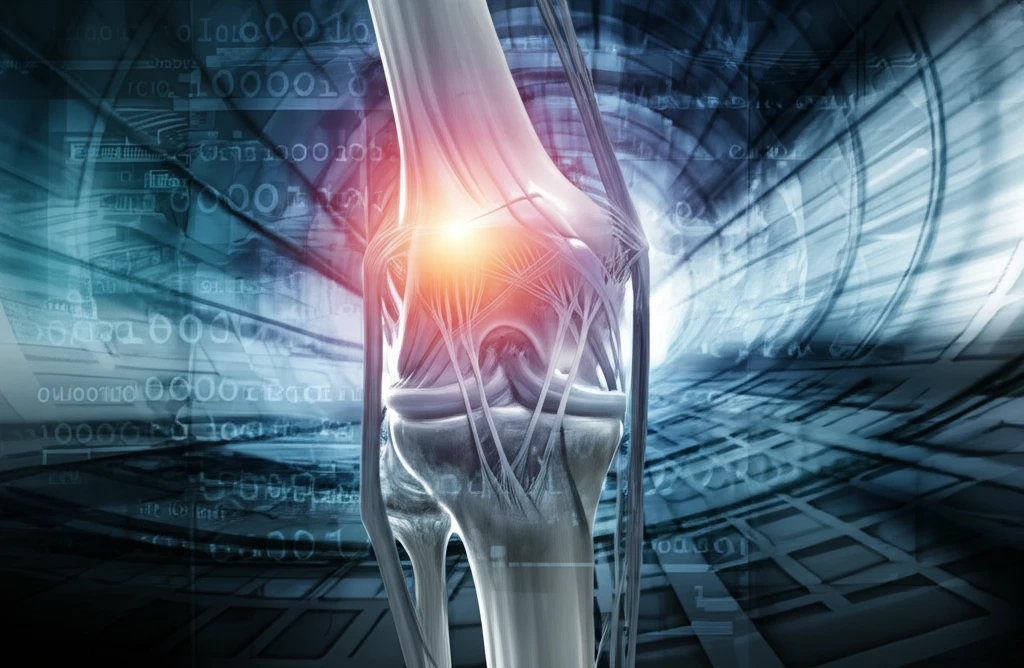

Knee injuries, especially those affecting the anterior cruciate ligament (ACL) and posterolateral corner (PLC), can significantly impact an individual's mobility and quality of life. While isolated ACL or PLC injuries are challenging enough, combined injuries present a complex scenario for orthopedic surgeons.

ACL reconstruction aims to restore stability and function to the knee joint, allowing individuals to return to their active lifestyles. However, when ACL injuries are coupled with damage to the PLC, the reconstruction process becomes more intricate. One of the key challenges lies in the precise placement of tunnels for graft fixation.

In combined ACL and PLC reconstruction, the close proximity of the tunnels created for graft placement raises the risk of tunnel intersection. This occurs when the tunnels for the ACL and PLC grafts converge or overlap within the lateral femoral condyle, potentially compromising the structural integrity of the bone and the stability of the reconstruction.